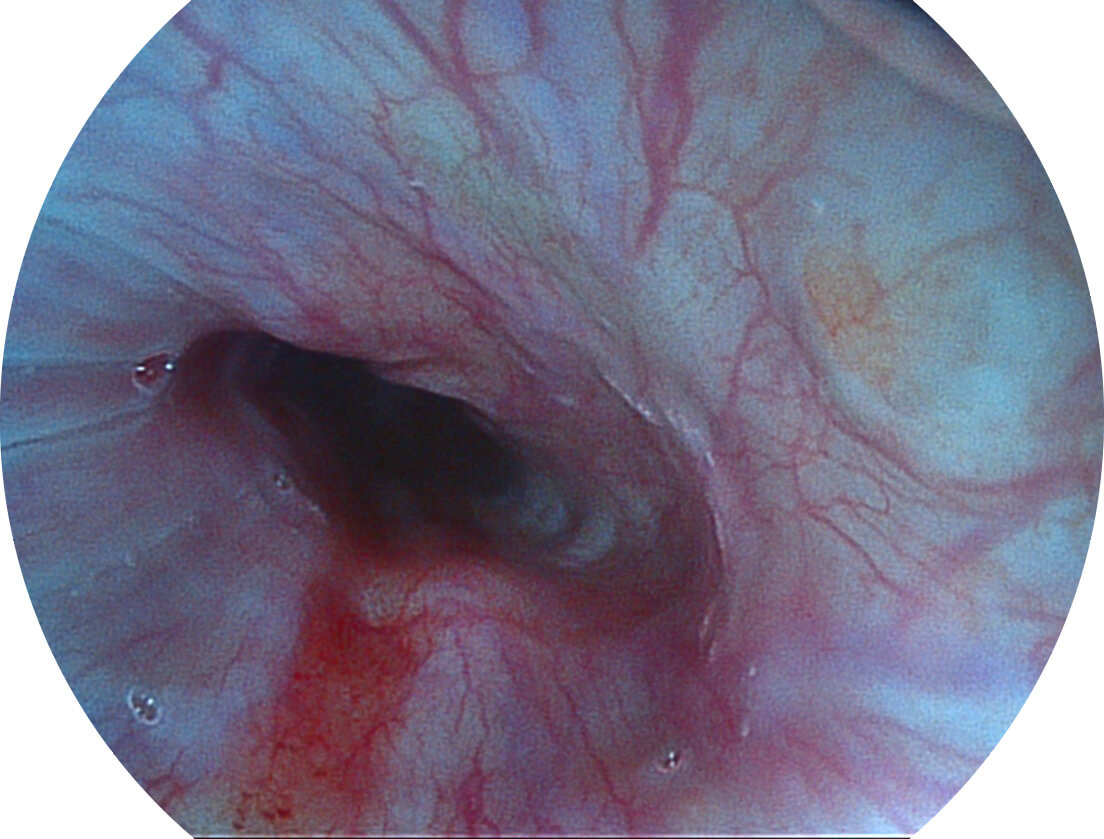

Spectral Focused lmaging, SFI

图像具有高亮度、高黏膜血管颜色对比度的特点,且不改变粘液、食物残渣、粪便的基本颜色,可在中远景下进行观察,助力消化道早期疾病的诊断。

SFI图像

白光图像